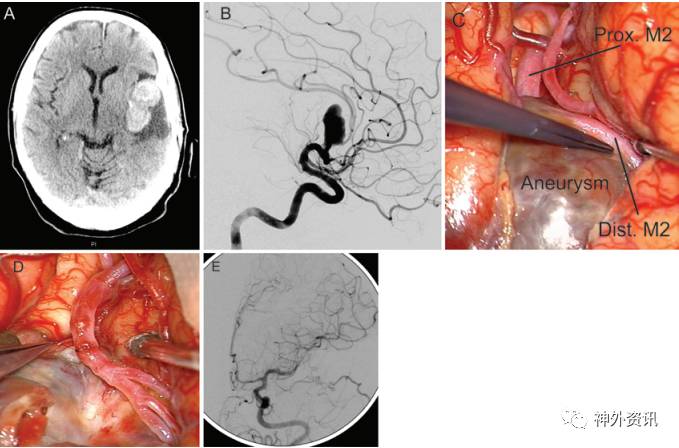

8例患者中6个动脉瘤将豆纹动脉移位,均被夹闭或切除。其中2个动脉瘤切除的同时进行血管再吻合(图3)。

图3. 分叉前动脉瘤。A.73岁男性颅脑CT轴位成像显示左侧巨大型MCA动脉瘤伴瘤内血栓形成;B.DSA显示有一支小血管从M1段近端至MCA分叉部间发出;C.分开外侧裂后,可见MCA近端至M1段血栓性动脉瘤;D.对MCA近端的M1段进行重建;E.术后DSA显示动脉瘤完全消失,MCA血运重建再通。